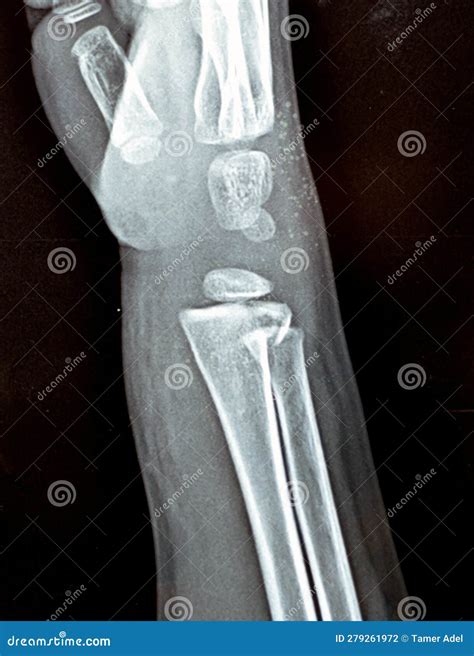

• Fractures: MRI can detect fractures that may not be visible on X-rays, especially in the early stages.

• X-Rays: Useful for detecting bone fractures and certain types of arthritis.

• CT Scans: Provide detailed images of bones and can be useful for detecting fractures and bone abnormalities.